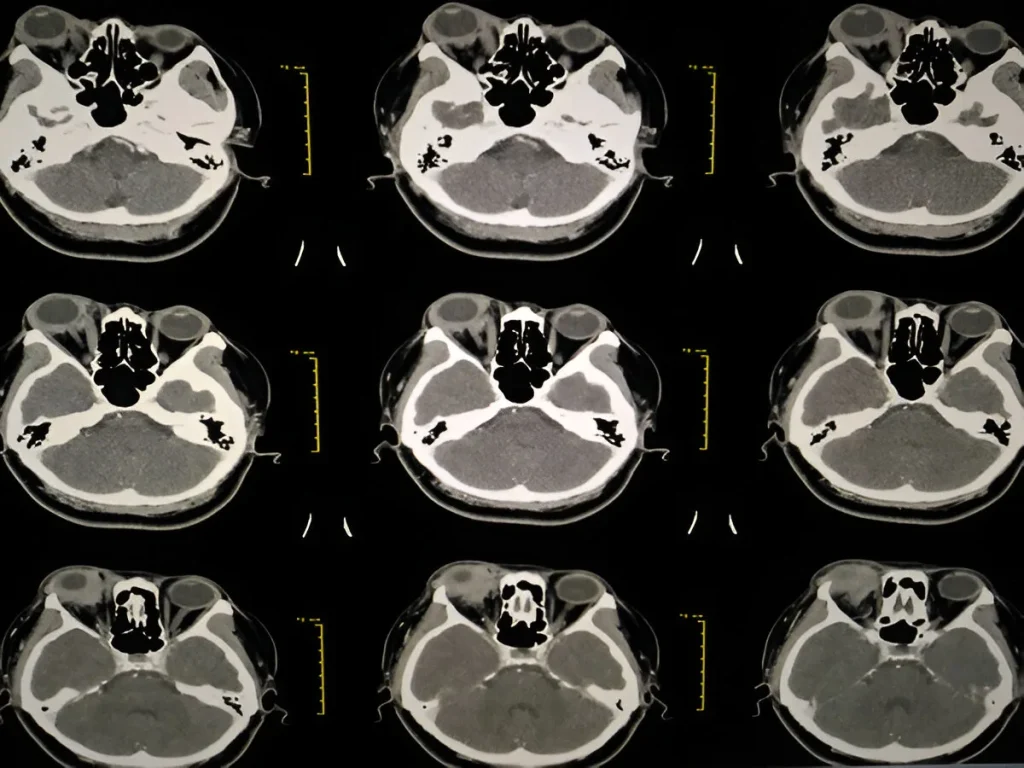

CT Brain in Navi Mumbai | Henotic Diagnostics

Looking for a CT Brain scan in Navi Mumbai? At Henotic Diagnostics, we provide advanced and accurate brain CT scans. Moreover, our high-resolution imaging helps detect strokes, head injuries, tumors, hemorrhages, and neurological conditions with precision. In addition, our expert radiologists and modern equipment ensure quick, detailed reports. We serve Kharghar, Panvel, Belapur, Vashi, Nerul, Airoli, Kamothe, Taloja, Kalamboli, and nearby areas. Therefore, for affordable care and reliable results, choose Henotic Diagnostics today.